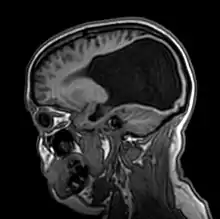

Colpocephaly is characterized by disproportionately large occipital horns of the lateral ventricles (also frontal and temporal ventricles in some cases). MRI and CT scans of patients demonstrate abnormally thick gray matter with thin poorly myelinated white matter. This happens as a result of partial or complete absence of the corpus callosum. Corpus callosum is the band of white matter connecting the two cerebral hemispheres. The corpus callosum plays an extremely important role in interhemispheric communication, thus lack of or absence of these neural fibers results in a number of disabilities.[12]

The lemon sign on CT scans of patients refers to the shape of the fetal skull when the frontal bones lose their normal convex contour and appear flattened or inwardly scalloped. This gives the skull a shape similar to that of a lemon. The sign is seen on transverse sonograms of the fetal cranium obtained at the level of the ventricles. A special case is found in literature where lissencephaly, colpocephaly, and septal agenesis are all present together. The CT scans of the patient shows the ventricular system having a unique appearance of a crown of a king. This is referred to as the 'CROWN SIGN'.[8]

After birth, MR imaging can be done to look for cephalic abnormalities. This is the most commonly used method for diagnosing colpocephaly. Physicians look for abnormally large occipital horns of the lateral ventricles and diminished thickness of white matter.[12] Spinal tapping is not a preferred method for diagnosis because newborn babies with colpocephaly or hydrocephaly have open fontanelles which makes it difficult to collect CSF. Also, colpocephaly is not associated with increased pressure.[13]